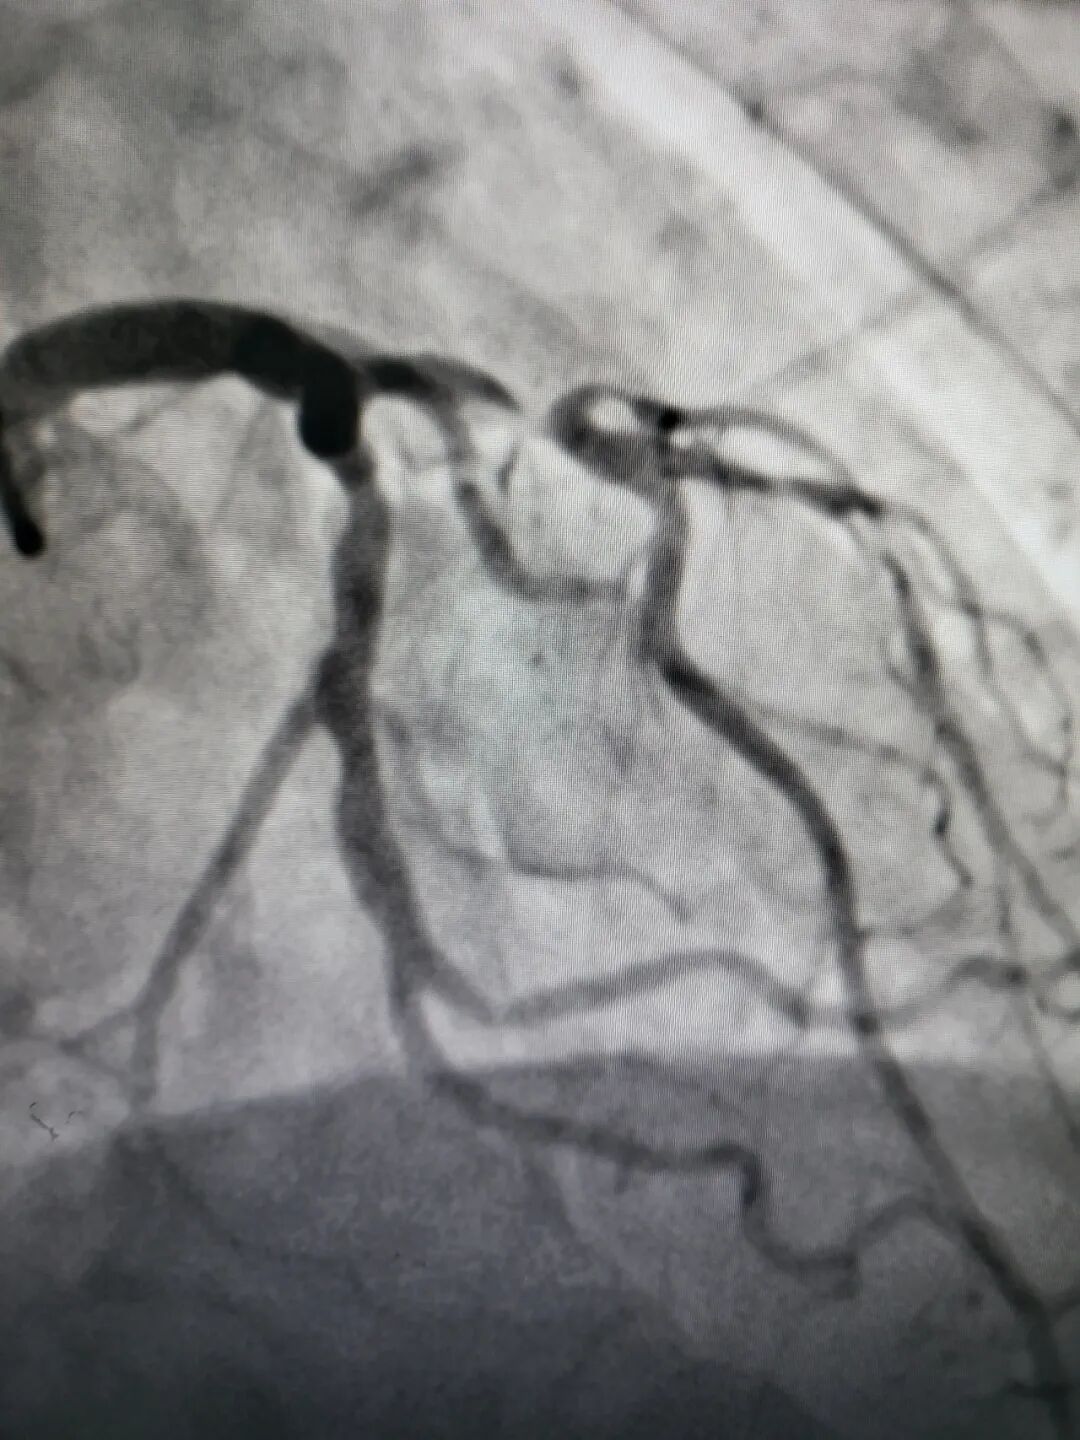

左前降支近中段CTO

右冠近段狭窄99%

左前降支近段狭窄99%

右冠近段次全闭塞

左前降支近中段弥漫性严重狭窄